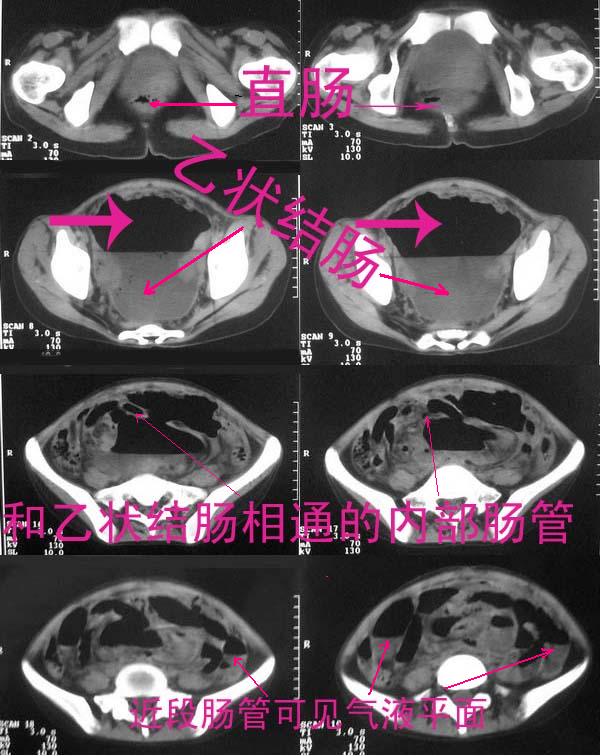

乙状结肠也扩张

直肠左侧低密度模糊影,乙状结肠明显扩张,有宽大液平,下腹部肠袢欠规整,内有多发小液平,结合有阑尾炎手术史考虑:直肠周围脓肿,低位肠梗阻,肠粘连。

盆腔巨大脓肿,据术者讲,脓肿大部分壁是有肠管壁形成的,少部分有自己较厚的壁,子宫、附件都泡在脓液里,腹腔肠管广泛粘连,这个病例奇怪的是急性发病,追问不出慢性病史。

考虑:肠粘连并低位肠梗阻;乙状结肠与回肠之间形成肠篓

结果收到,谢谢楼主,对照结果,回过头看,乙状结肠后壁液性低密度影应该也是脓肿。